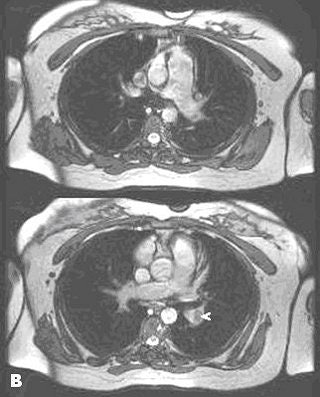

![]() |

| Noncontrast-enhanced MR of pulmonary embolism. A 36-year-old woman, 12 weeks pregnant, presented with shortness of breath. Coronal (above) and axial (below) and axial FIESTA views demonstrate left main pulmonary artery embolus (arrowheads). Images courtesy of Dr. Patrick Colletti. |